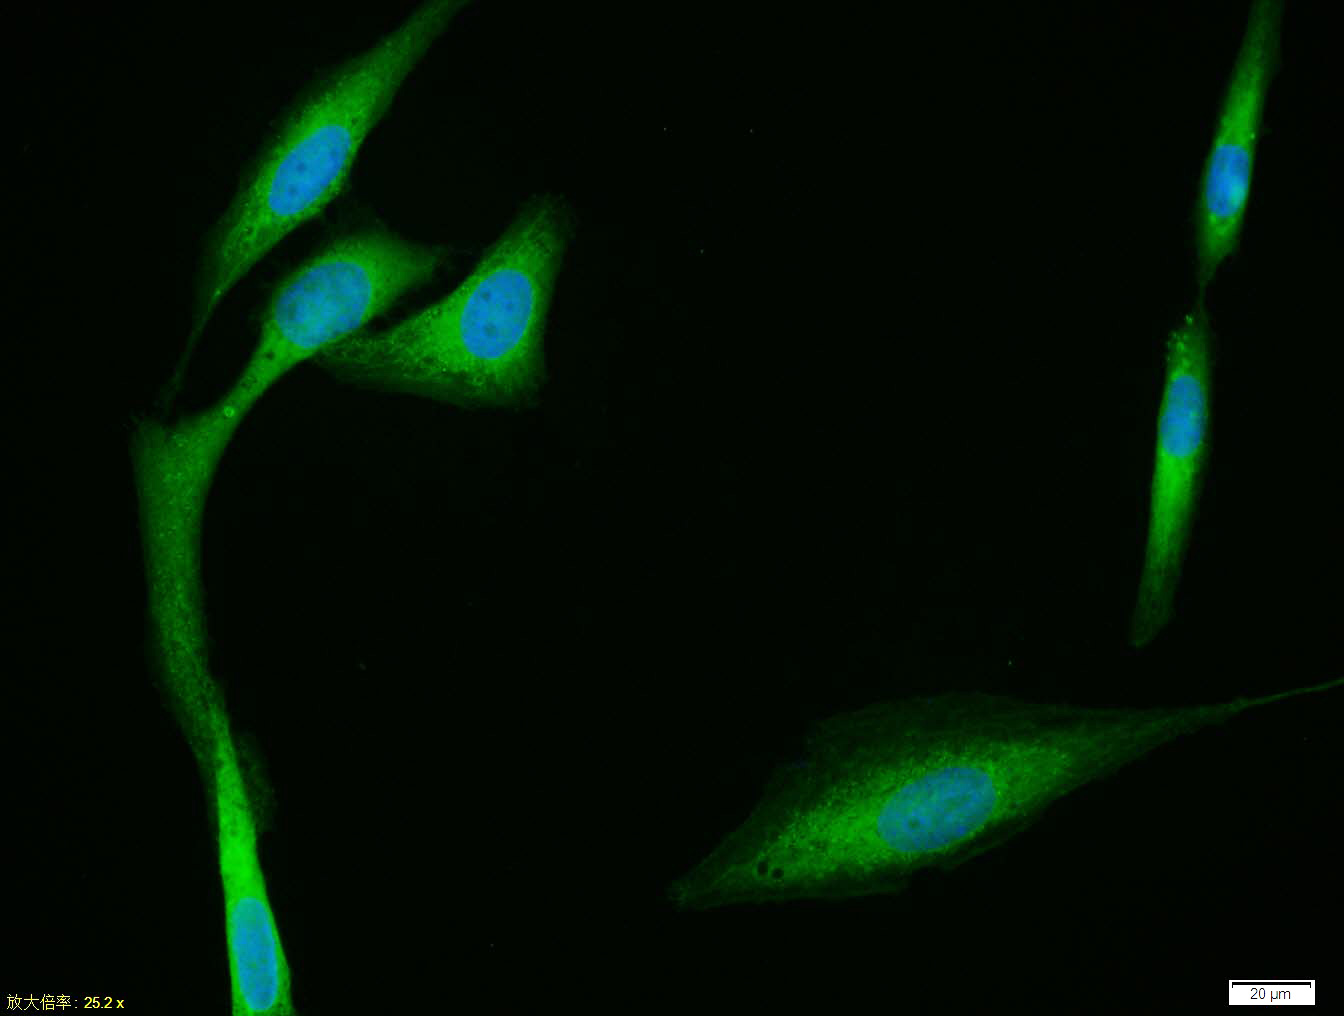

U-2OS cell; 4% Paraformaldehyde-fixed; Triton X-100 at room temperature for 20 min; Blocking buffer (normal goat serum, C-0005) at 37°C for 20 min; Antibody incubation with (CYP24A1) polyclonal Antibody, Unconjugated (bs-3899R) 1:100, 90 minutes at 37°C; followed by a conjugated Goat Anti-Rabbit IgG antibody at 37°C for 90 minutes, DAPI (blue, C02-04002) was used to stain the cell nuclei.